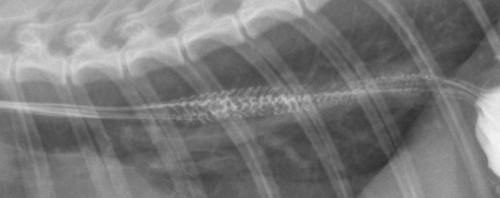

1つ注意点としては、ネコちゃんのバリウム造影を実施する場合、食道内に以下のような造影増強が見受けられることがあります。

図8. 猫の食道に見受けられる“Herringbone Sign”。

これは“herring bone(ヘリンボーン、直訳:ニシンの骨)”模様といわれ、ネコちゃんの食道の構造状、このように造影増強される正常所見であり、閉塞と見間違えられることもあるので注意が必要です。